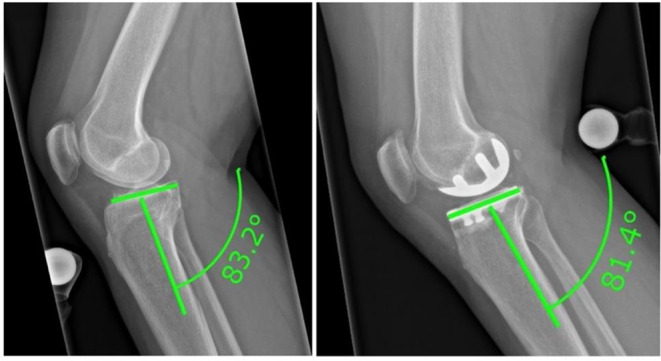

Methods: This retrospective study analyzed 63 patients with cemented medial UKAs with a minimum follow-up of five years. Patient-reported outcomes (PROMs) included the Oxford Knee Score (OKS). Radiographic parameters assessed were: PTS, mechanical axis, prosthetic joint space height, tibial component obliquity, intraprosthetic divergence, and tibial periprosthetic radiolucency. Partial Pearson correlation and multiple linear regression analyses were used to evaluate the relationship between tibial periprosthetic radiolucency and demographic or radiographic parameters.

Results: Of 63 patients (mean age 68.9 ± 7.9 years, follow-up 62.5 ± 8.8 months), 5 knees (7.9%) demonstrated tibial periprosthetic radiolucency ≥ 2 mm. The mean postoperative PTS change was 3.8 ± 2.6°, mechanical axis change: 2.5 ± 1.8°, prosthetic joint space height: 9.2 ± 3.1 mm, tibial component obliquity: 2.5° ± 3°, and intraprosthetic divergence angle: 5° ± 4°. OKS averaged 43.9 (range 22-48), with a mean knee flexion of 123.4 ± 6.8°. Statistical analysis showed no significant associations between tibial periprosthetic radiolucency and demographics, radiographic parameters, or PROMs. Changes in PTS did not correlate with a range of motion (ROM), PROMs, or radiolucency.